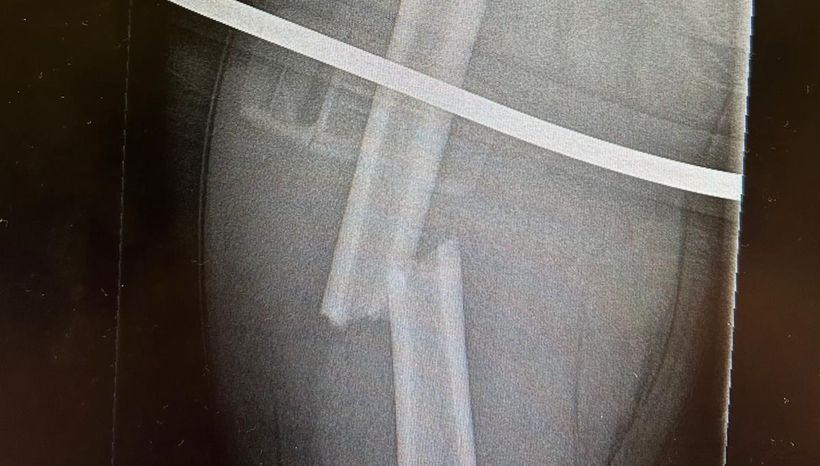

Seb, who has been racing since he was six years old, had broken his femur (thigh bone) resulting in immense physical pain for the child.

Thanks to the speed of our air ambulance, Seb’s leg was operated on the very same day. Two titanium rods were fitted into his leg, both of which will be removed in roughly two years’ time.